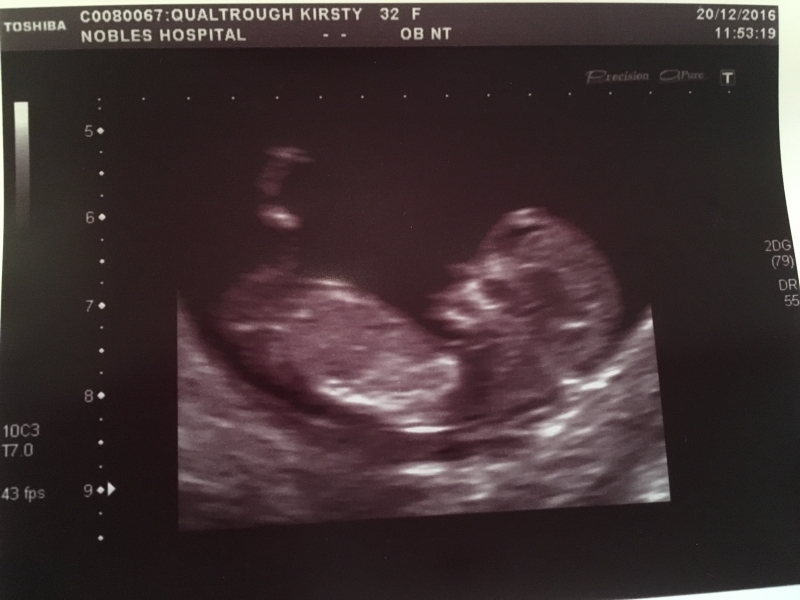

What a month! Along with the usual run-up to Christmas festivities (mince pie making, winter walks with Mum and Lass, Christmas shopping and wrapping) we had the added enjoyment/excitement of having our first baby scan!! On 20th December we went to Nobles for an ultrasound where we saw our little one for the first time - moving around in it's little uterus play-pen! It was a really amazing moment seeing it on the screen for the first time, confirming the reality of us becoming parents in just over 6 months time! The sonographer was able to tell us that I was 11 weeks 3 days along, with a due date of 8th July 2017 Once we had the scan pictures we broke the news to the family over the next few days (having already told my Mum on the day she came back from New Zealand!). I would say that Christmas this year was a fairly chilled event - to be honest I didn't have the usual energy or motivation....and not being able to share in the fizz/beer/wine/port made things slightly more low key (yet healthier!) than other years! But it was really nice to be able to chill (I stayed at mum's from 22-26th and then at Glenn's for a few days while Max and Zoe were over), play games, take naps, eat when I liked (which I did a lot of!) and be as energetic as I liked 🙂 While at mum's we got out for plenty of nice walks up in the hills and played games in front of the fire, and at Margie's we also played games, ate lots of roasts and had a trip out to hunt for wallabies 🙂 New Year's Eve was also a quiet affair - we went down to the Duggan's for the buffet and chit chat and joined the family for part of the pub crawl (even though it was windy and wet!) to the Bay, Falcs and Station before we retired back to Failt Erriu (about 10.30pm) where we chilled with Mum and welcomed 2017 in with hugs and excited expectations for the year to come. After a lovely Christmas break it was nice to get back to the flat, clear away the Xmas tree and deccy's and get back into some sort of 'normal' routine (for a while at least!). We've got more midwife appts and scans happening over the next few months, and lots of decisions to make about work/living etc so watch this space for updates! Here's a few pics from over the Christmas period: